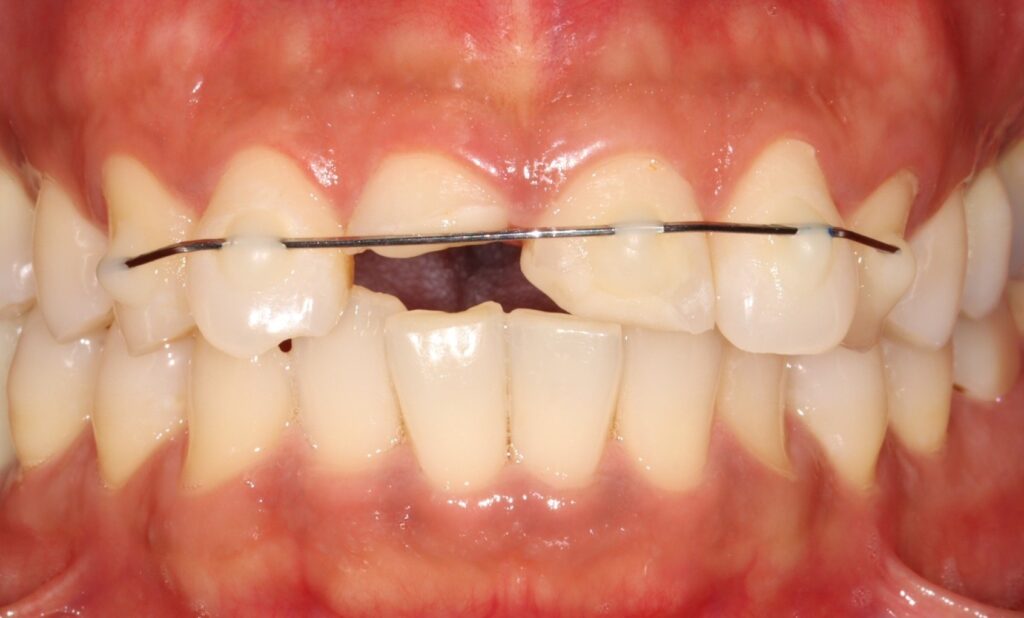

예시 사진을 보면

앞니의 2/3이상이 부러져 사라진 것을

확인할 수 있는데요.

2025.02.12

그로 인해 11번의 경우

자연치 내부 치수가 드러난 것을

볼 수 있으며,

21번은

치수가 드러나지 않았지만

많은 양의 치질이 사라져 있습니다.

이것은 흔들리거나

부분 탈구된 치아를 안정화시켜

치유를 돕는 치료입니다.

골절과 같이 심한 경우에는

4주 정도의 단단한 고정이 필요합니다.

단순한 치아 흔들림의 경우

2주에서 4주 정도 유지합니다.

철사와 레진을 사용한 고정이

가장 일반적으로 사용되며

치유 후에는 제거해야 됩니다.